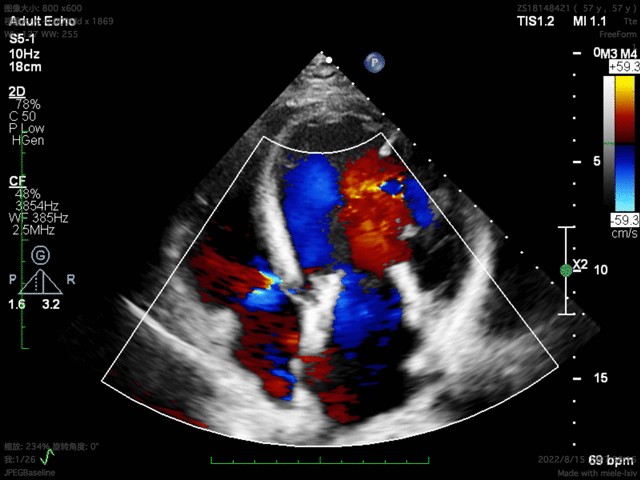

术后30天随访结果

患者术后30天随访状态良好,随访显示左心室逆重构,左心室功能伴左心室结构显著改善,全面达成包含二尖瓣反流程度降低、心功能改善等有效性指标。人工二尖瓣工作正常,支架结构及形态稳定,锚固良好无位移,无瓣周漏。瓣叶开闭形态良好,血流动力学表现优异,平均跨瓣压差仅1mmHg。